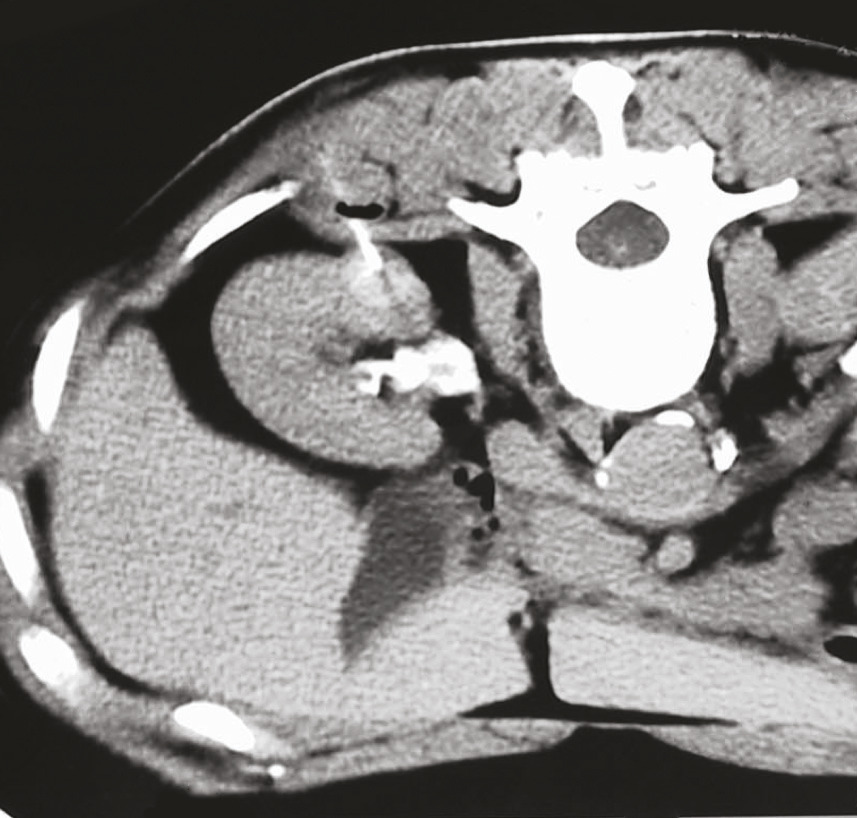

La biopsie des masses rénales est actuellement bien standardisée et codifiée. Elle est généralement réalisée par un radiologue, sous anesthésie locale, en externe ou en ambulatoire. Le guidage classique est un guidage tomodensitométrique (fig. 1). Certaines masses rénales faciles d’accès peuvent être biopsiées sous guidage échographique. Au moins deux prélèvements sont réalisés en évitant les zones de nécrose. Pour les tumeurs avec plusieurs contingents radiologiques, les contingents radiologiques différents doivent être prélevés. Une aiguille fine coaxiale (18 gauges) est utilisée pour protéger le trajet de ponction d’une contamination tumorale.3 Il est recommandé que le patient soit à jeun pour prévenir les nausées et vomissements réflexes éventuels. Un contrôle tomodensitométrique post-biopsie est réalisé avant le départ du patient pour vérifier l’absence de saignement rénal. Un rendez-vous de consultation est programmé avec l’urologue référent pour la communication du diagnostic et la décision de la réunion de concertation pluridisciplinaire d’oncologie.